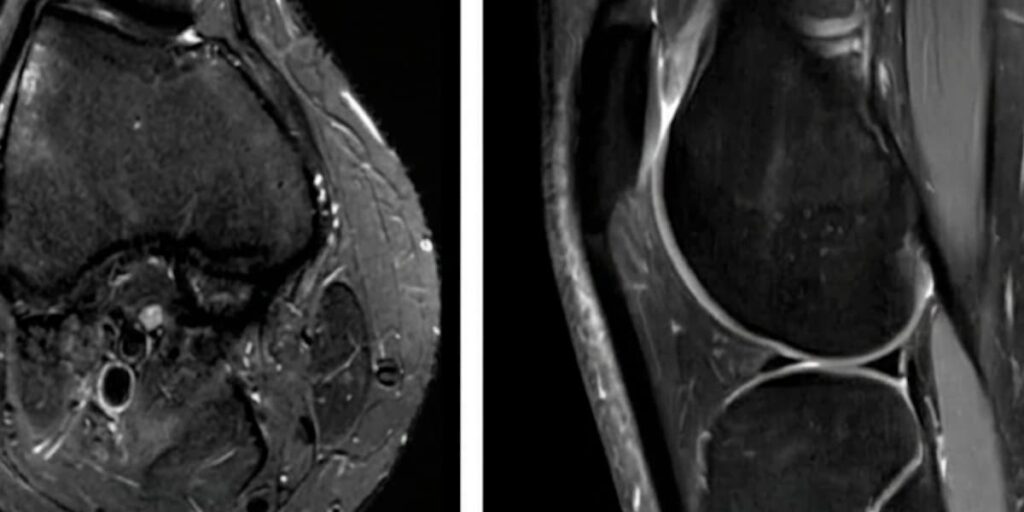

Knee Chondromalacia Symptoms & Treatment

You may be suffering from a condition called knee chondromalacia or chondromalacia patella if you’ve been experiencing dull, achy pain around or under your kneecap. In the past, any pain over the kneecap or patella (the anterior aspect of the knee) was often referred to as patellofemoral chondromalacia, but it actually describes a specific condition. […]